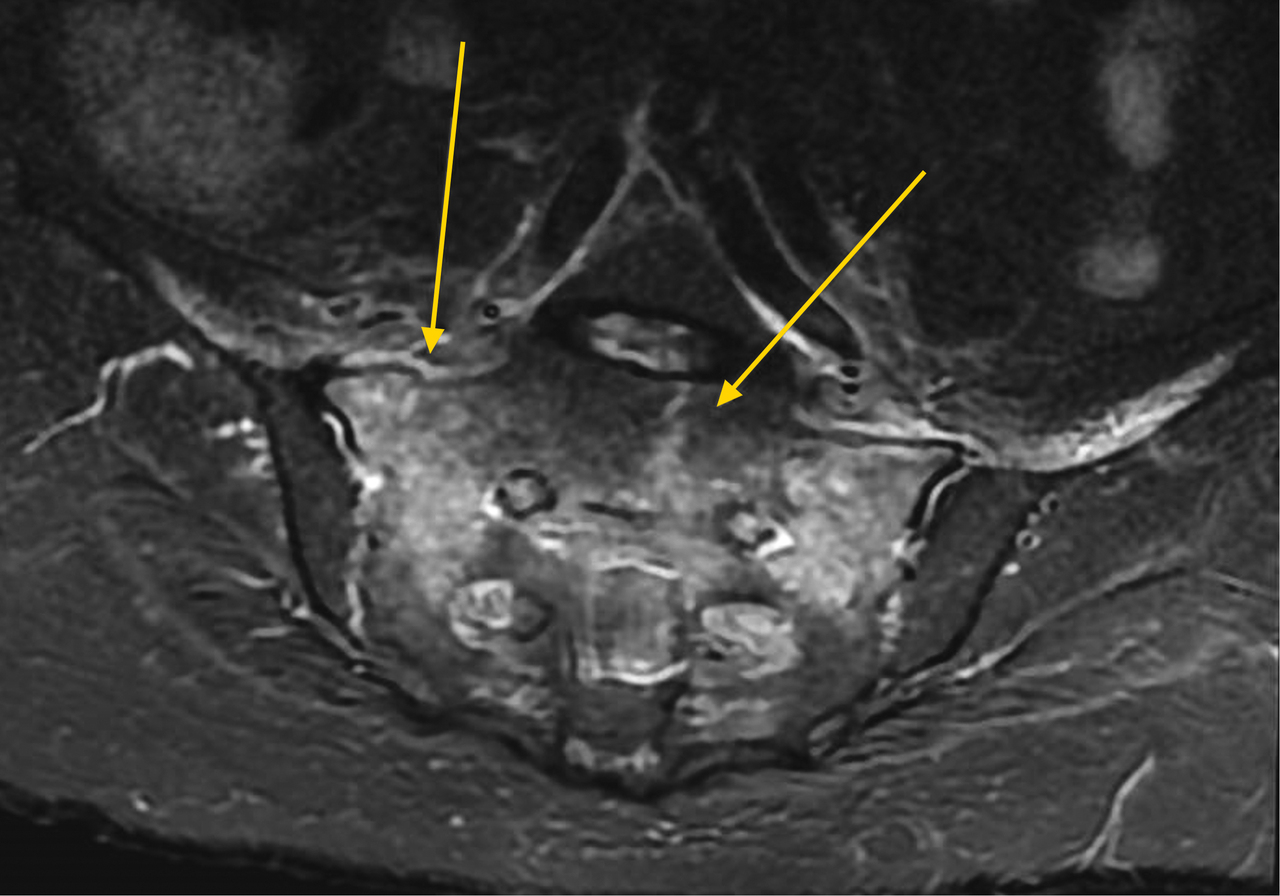

Les fractures du sacrum par insuffisance osseuse (ostéoporose) sont une pathologie fréquente du sujet âgé mais sous-estimée. Le diagnostic est rarement suspecté et une errance de plusieurs mois est fréquente. La fracture du sacrum est confirmée par une imagerie par résonance magnétique ou une scintigraphie mettant en évidence la solution de continuité d’une ou des 2 ailes sacrées pouvant être reliées entre-elles et réalisant ce que l’on appelle communément la fracture en « H » du sacrum. La symptomatologie est aspécifique mais la présence d’une douleur lombaire basse chez un patient ostéopénique doit faire évoquer le diagnostic.